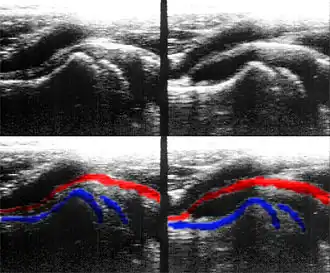

Sonografie einer normalen (links) und entzündeten (rechts) Hüfte eines Kindes. Unten nachträglich blau gefärbt: Knochengrenzen (jeweils links Schaft, rechts Kopfkern, getrennt durch Wachstumszone) rot gefärbt: Kapsel.

Im 2D-Echtzeitmodus, der derzeit häufigsten Anwendung des Ultraschalls, wird ein zweidimensionales Schnittbild des untersuchten Gewebes durch automatische Verschwenkung des Messstrahls und Synchronisierung der B-mode-Darstellung in Echtzeit erzeugt. Das Schnittbild wird dabei aus einzelnen Linien zusammengesetzt, wobei für jede Linie ein Strahl ausgesendet und empfangen werden muss. Die Form des erzeugten Bildes hängt dabei vom eingesetzten Sondentyp ab. Der 2D-Echtzeitmodus kann mit anderen Verfahren wie dem M-Mode oder der Doppler-Sonografie gekoppelt werden. Je nach Eindringtiefe und Sondentyp können nur einige wenige oder bis zu über hundert zweidimensionale Bilder pro Sekunde dargestellt werden.